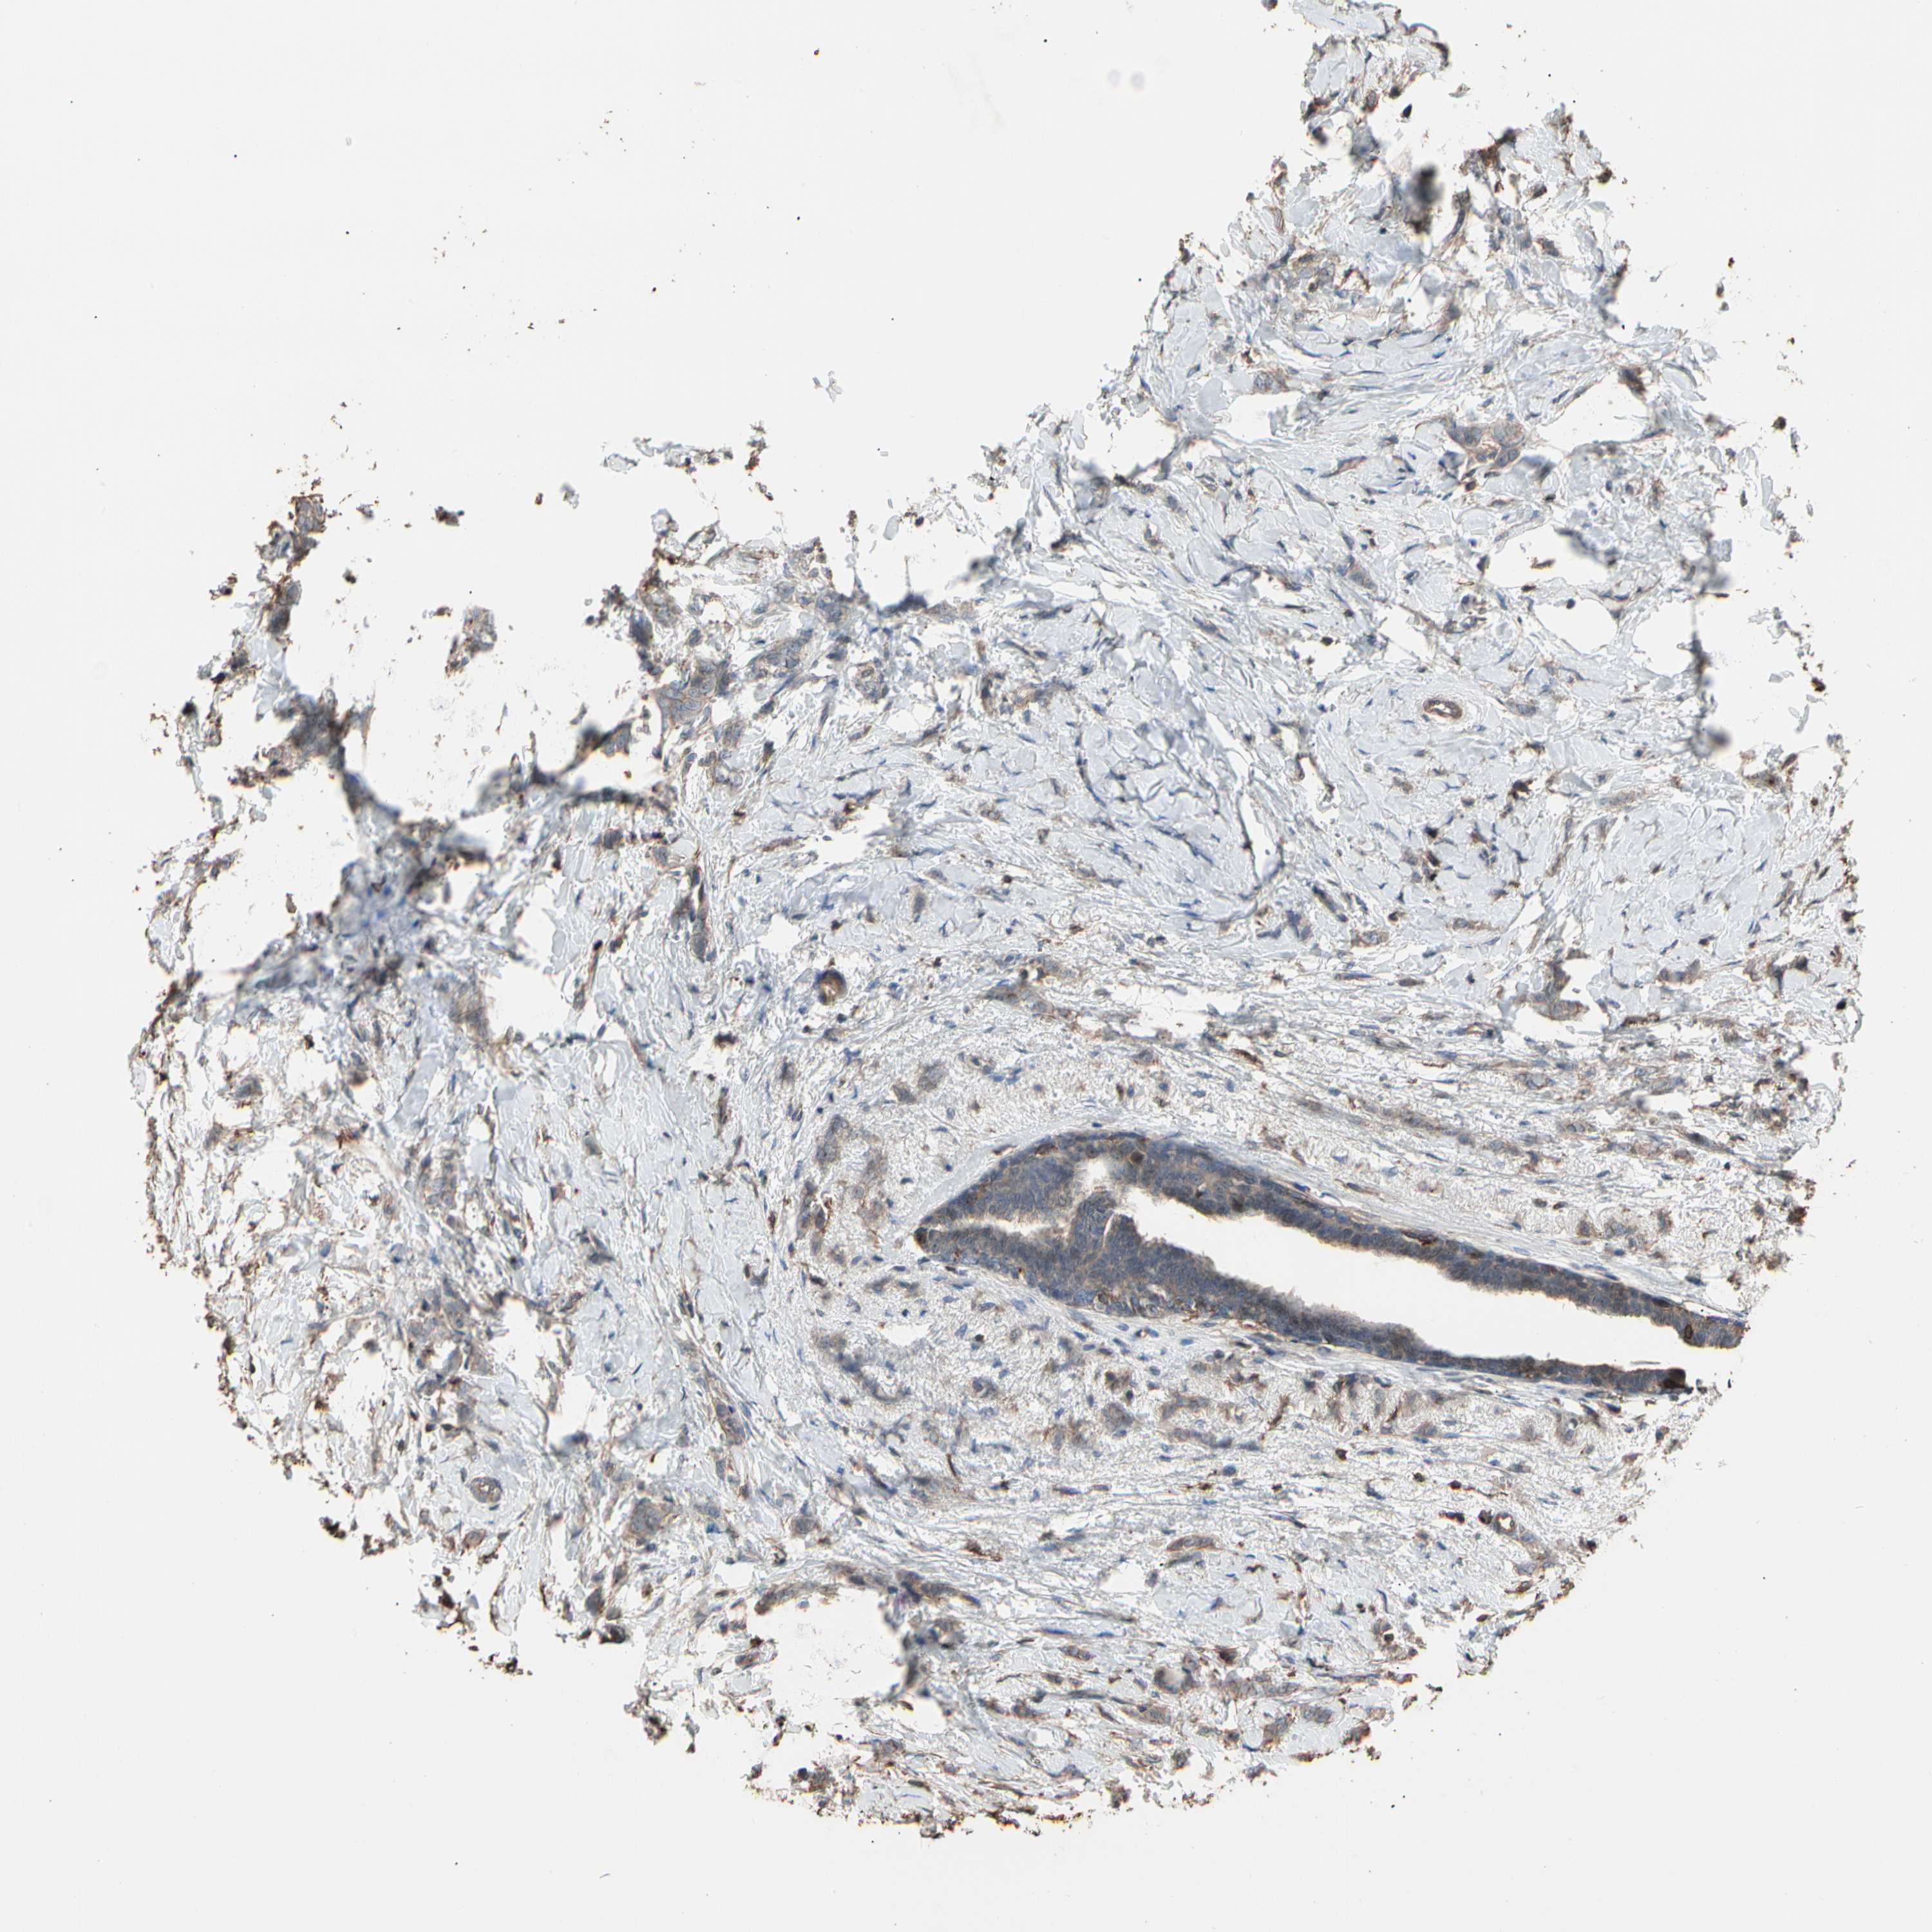

BRCA TCGA BRCA VALIDATION PROTEIN EXPRESSION

ANTIBODIES

AND

VALIDATION